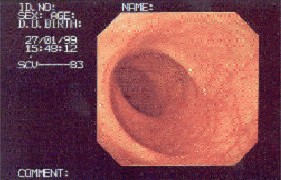

자궁경부암 환자의 자궁경부 이미지

[자궁경부암 환자의 자궁경부]